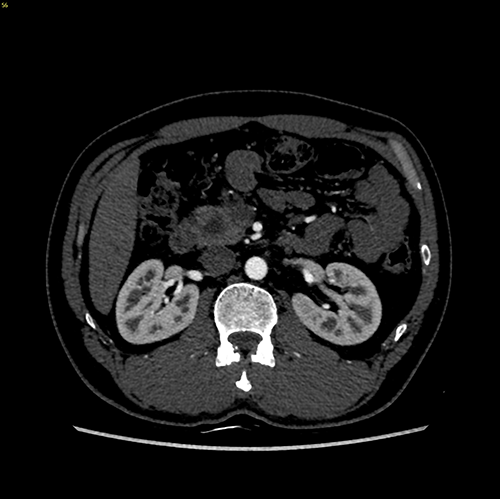

肿块型慢性胰腺炎----胰十二指肠切除